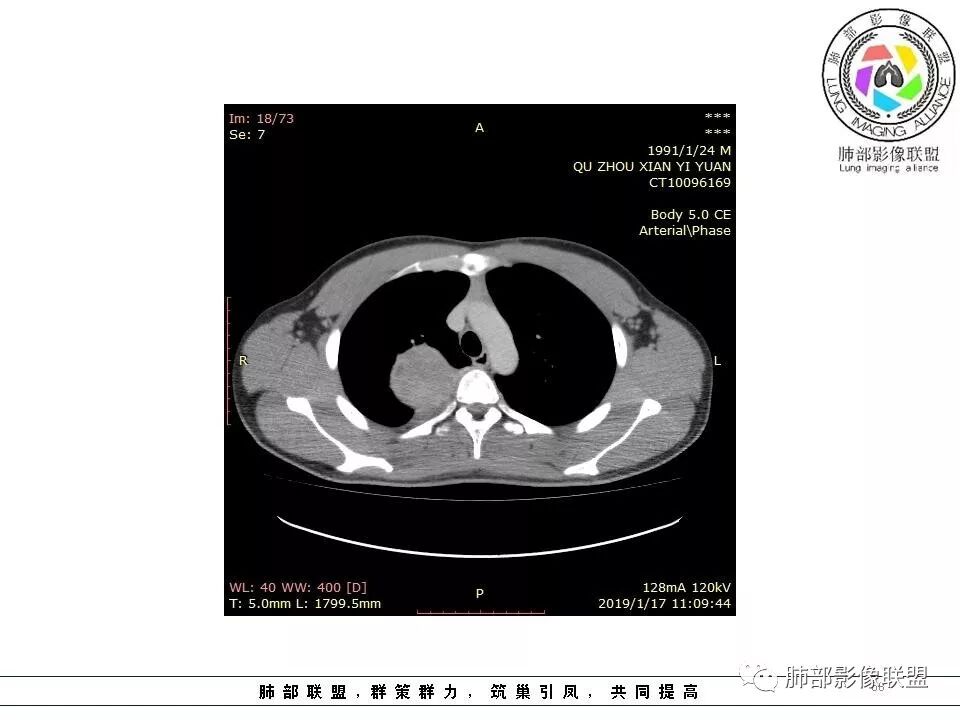

青年男性,间断胸痛;右侧脊柱旁可见一类圆形软组织密度影,密度欠均匀,增强扫描呈轻中度持续强化,邻近肺组织及肺动脉推移,可见肋间动脉供血,部分胸膜下脂肪可见,部分层面似见与右侧椎间孔相连。考虑后纵隔神经源性肿瘤。

青年男性,间断胸痛。右后纵膈脊柱旁软组织占位,形态规则类圆,边缘光整,肺组织受压,D字征,胸膜尾,肋间动脉供血。中度不均匀延迟强化。无支气管进入考虑来源于肺外、肿块与脊柱间未见明显脂肪间隙,考虑来源于胸膜外,考虑神经源性肿瘤,建议穿刺活检。

青年男性,右侧脊柱旁软组织肿块,边缘膨隆,密度不均,临近肺组织受压、胸膜增厚,增强后动脉期呈不均匀强化,并可见肋间动脉供血,延迟期强化较均匀,定位肺外,首先考虑SFT,神经源性肿瘤待排

右肺占位,跨越上叶后段、下叶背,边缘光滑,瘤肺界面清,见肺压缩缘(线样不张`强化),见胸膜尾征,胸膜下脂肪未见明显增厚,肋骨丶脊柱未见侵袭及受压,渐进性丶地图样强化,冠状位似见体循环供血

诊断:SFT(来源壁层胸膜?一般小于20%)

鉴别:神经源性(鞘瘤)、LCD、肉瘤丶孤立性间皮瘤

青年男性,右后上纵隔脊柱旁沟可见团状软组织影,边界清,密度尚均匀,推挤邻近肺组织,胸膜可见掀起,有肺动脉供血,增强轻度蛇皮样强化,纵隔淋巴结未见肿大,邻近骨质未见破坏,胸膜下脂肪间隙消失,考虑SFT孤立性纤维瘤可能性大,鉴别神经鞘瘤,节细胞瘤,建议活检。

青年男性,胸痛,右上纵膈脊柱旁肿块,形态光整规则,支气管被推移,临近的胸膜明显增厚,有胸膜掀起,增强后密度不均匀,可见蛇形血管征,血供似乎有两根血管供血,考虑SFT

边缘光滑,宽基底与胸壁相连,跨叶裂,叶裂稍前推,血管、支气管前移。

浅分叶

外上侧少量胸水

肋间动脉供血,强化尚均匀,逐步强化

1.右上胸内脊柱旁类圆形肿块,质地似乎比较坚实,密度稍显不均,但未显示明确的坏死。

2.肋间动脉病供血也提示肿块来自后纵隔?